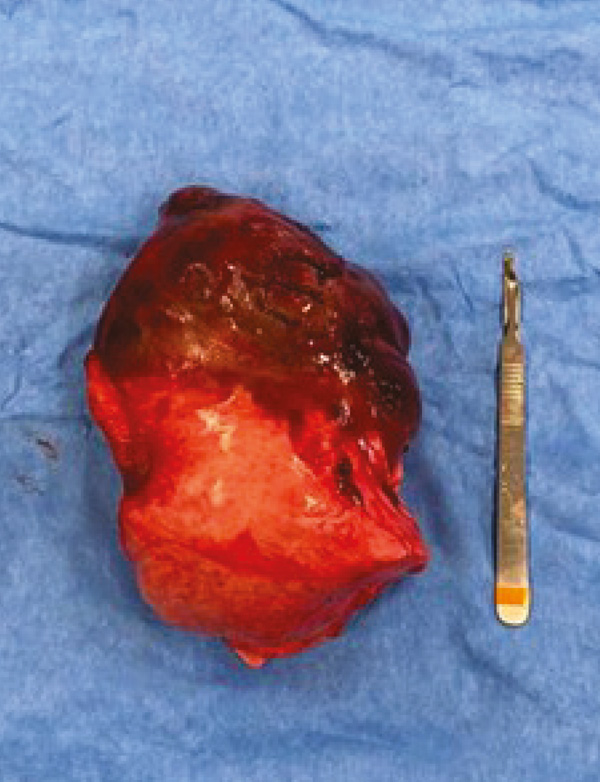

Figure 7: Right caudal lung lobe and associated mass.

Histopathological results of the mass was a poorly differentiated soft tissue sarcoma. These tumours carry a high potential for local post-surgical recurrence. In this case, metastatic potential was difficult to predict due to the poor differentiation of the neoplasia.

Survival times for animals showing primary pulmonary neoplasia vary greatly and can go from 26 to 545 days, depending on clinical signs and metastatic spread.9 This dog was considered to have a good prognosis given that this was a solitary mass and no malignant plural effusion, lymph node involvement or metastatic disease were detected at the time of surgery.9 However, the poor differentiation of the neoplasia and its size (i.e., being bigger than 5cm) are negative prognostic indicators.9 Moreover, despite CT dramatically improving detection of metastatic disease when compared to radiographs, it can still be associated with false-negative results.9 These tumours can also be highly infiltrative and, given the initial tumour location and difficulty of excision, failure to obtain clear margins cannot be excluded. For these reasons, owners were strongly advised to perform a recheck CT, ideally within the following six-12 months, to allow for monitoring for tumour recurrence and/or metastatic disease.